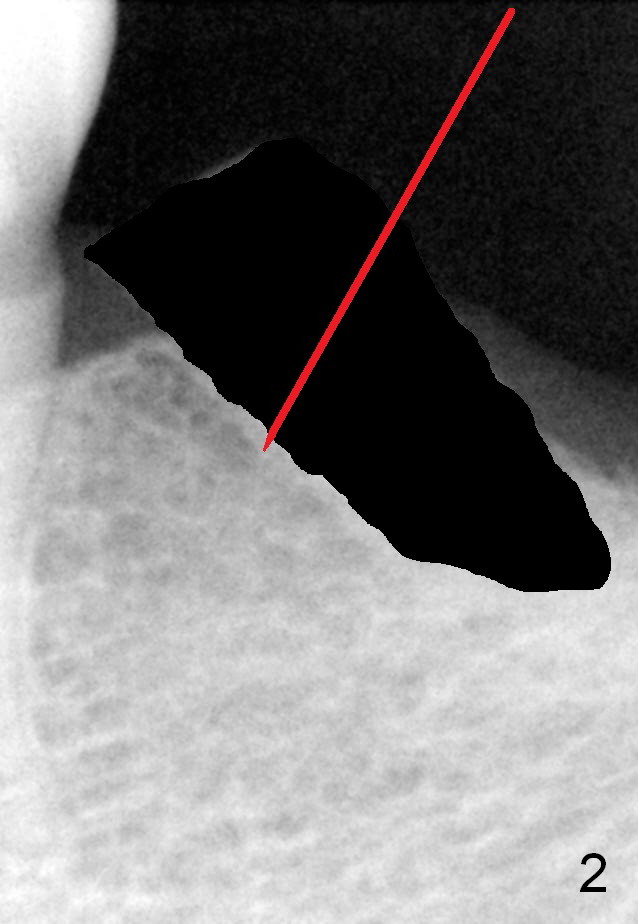

A 78-year-old lady is scared of dentistry, but she has no problem having a 2nd immediate implant (#20 in Fig.1) once the 1st one turns out to be without pain. The challenge associated with #20 is its long axis. After extraction, the osteotomy is initiated in the mesial socket wall at the junction of the upper and middle 1/3 obliquely (Fig.2, slightly lingually). Once the entry is obtained, the axis of the pilot drill is changed to be parallel to the neighboring tooth (Fig.3); an implant spacer of 2.5 mm is used to check (against the 2 mm pilot drill) so that the center of the osteotomy is 3.5 mm from the neighboring tooth (Fig.4). The implant will be 4.5x14 mm. The depth is not longer than that of the neighboring tooth so that it should be quite safe relative to the Mental Loop and the Inferior Alveolar Canal (yellow dashed line in Fig.1). The apical socket is packed with collagen dressing while the coronal one with bone graft. An immediate provisional will be fabricated to keep the graft in place. The osteotomy should be as lingual as possible to avoid the Mental Loop (Fig.1' red dashed line).